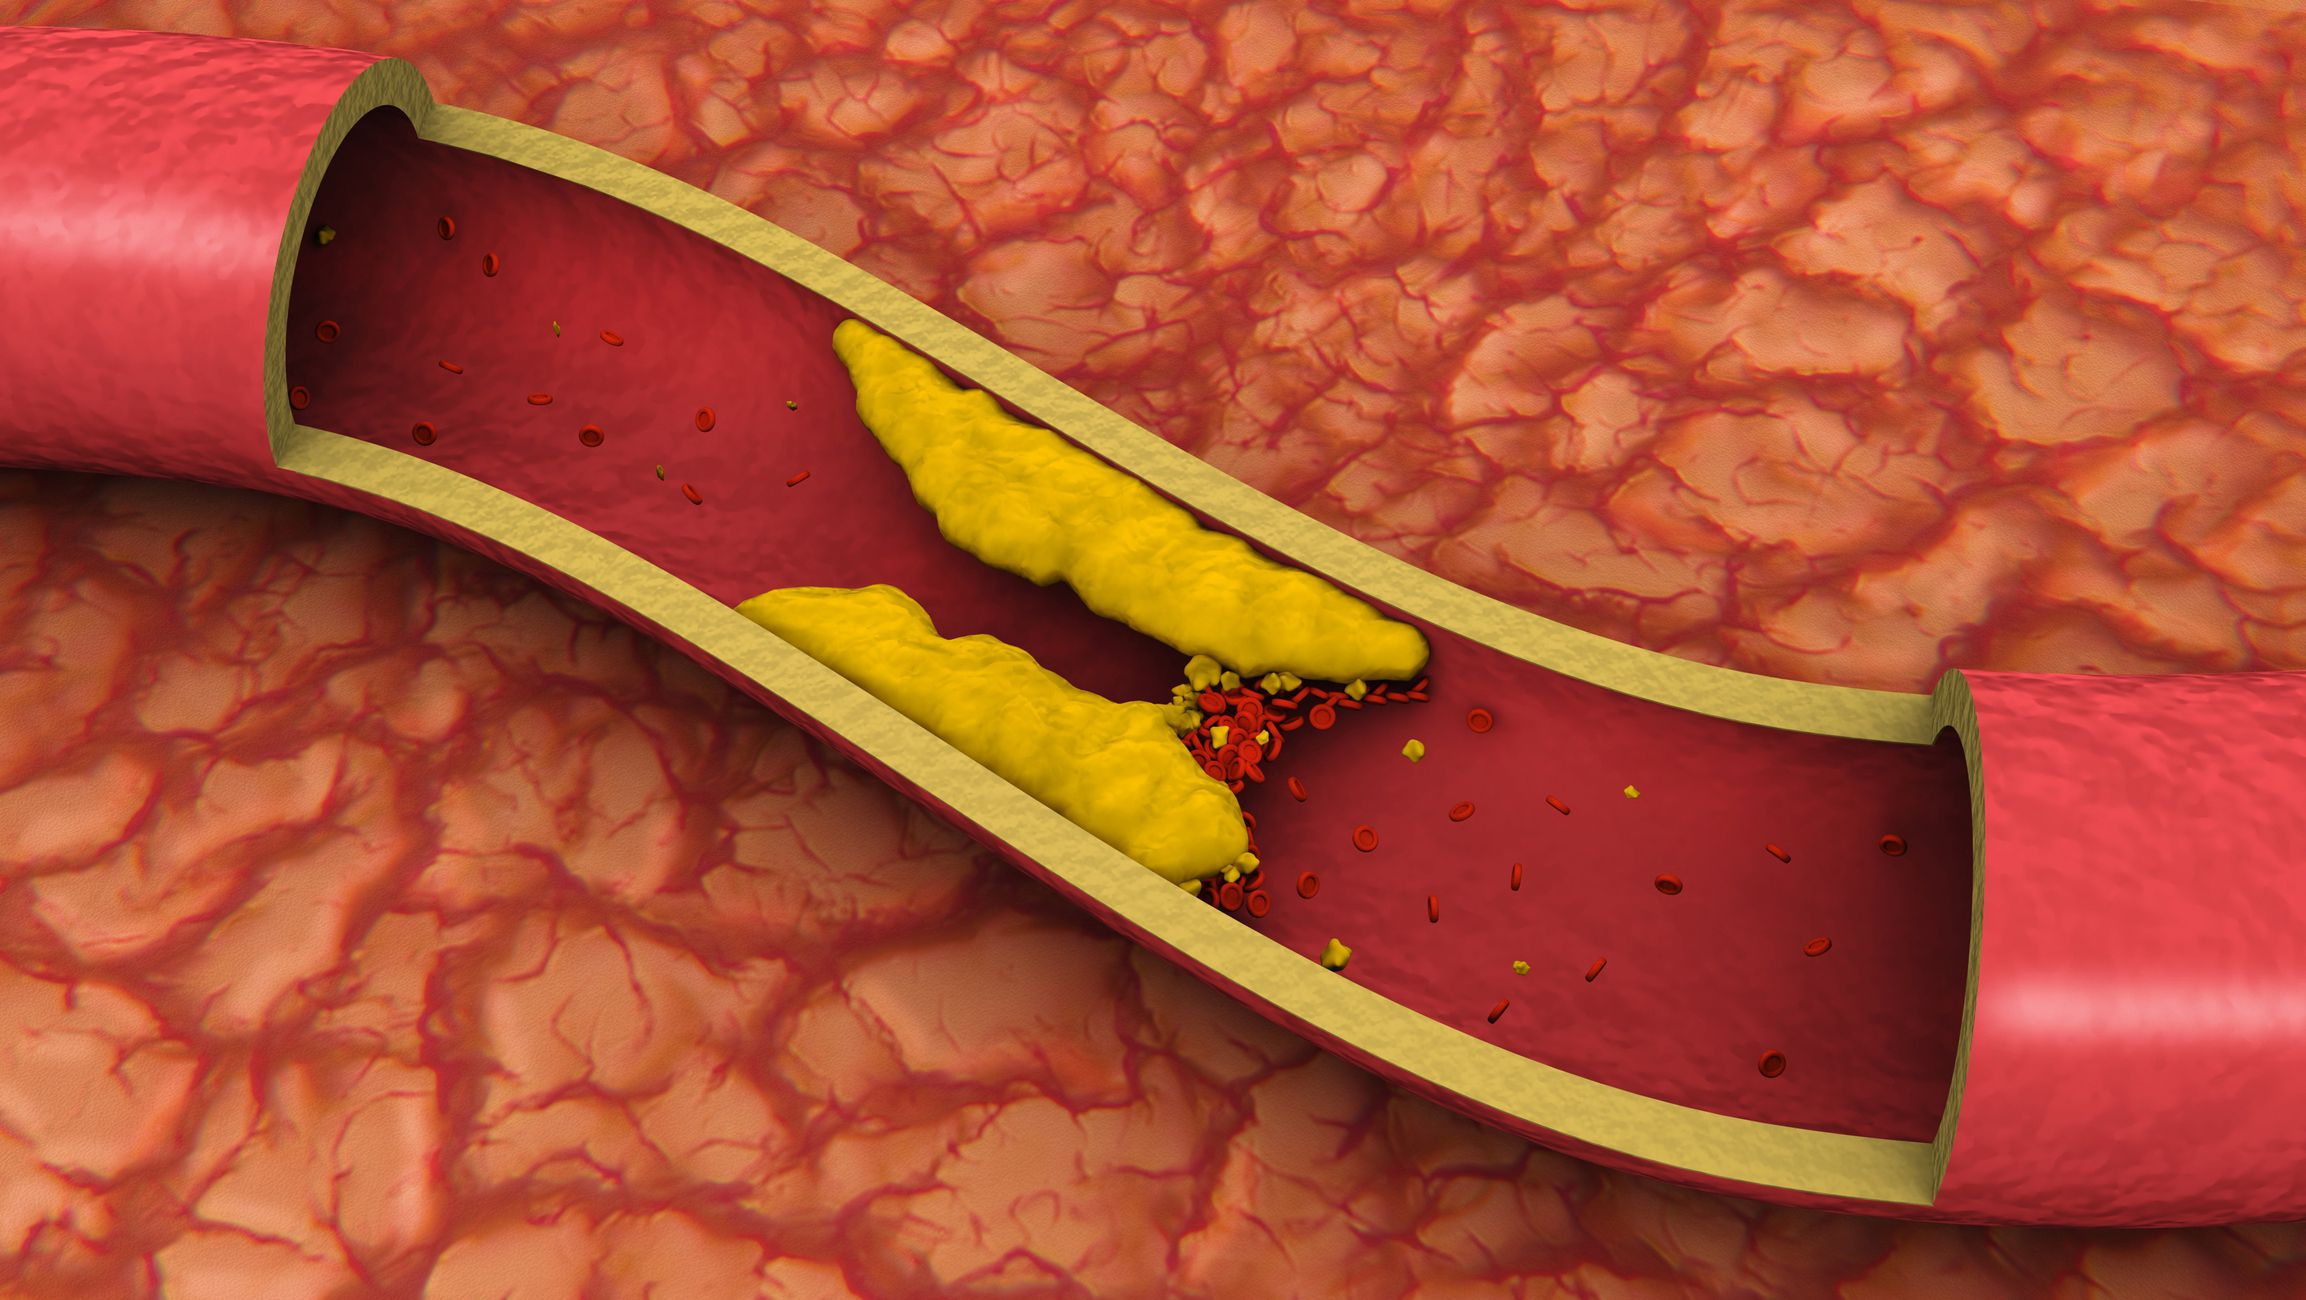

Холестерин в организме: влияние и функции (схемы и диаграммы)